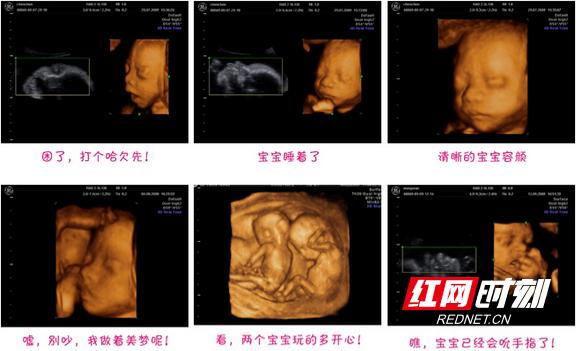

b超检查中宝宝的各种姿态.

b超中的胎宝宝,千姿百态好可爱__网易亲子